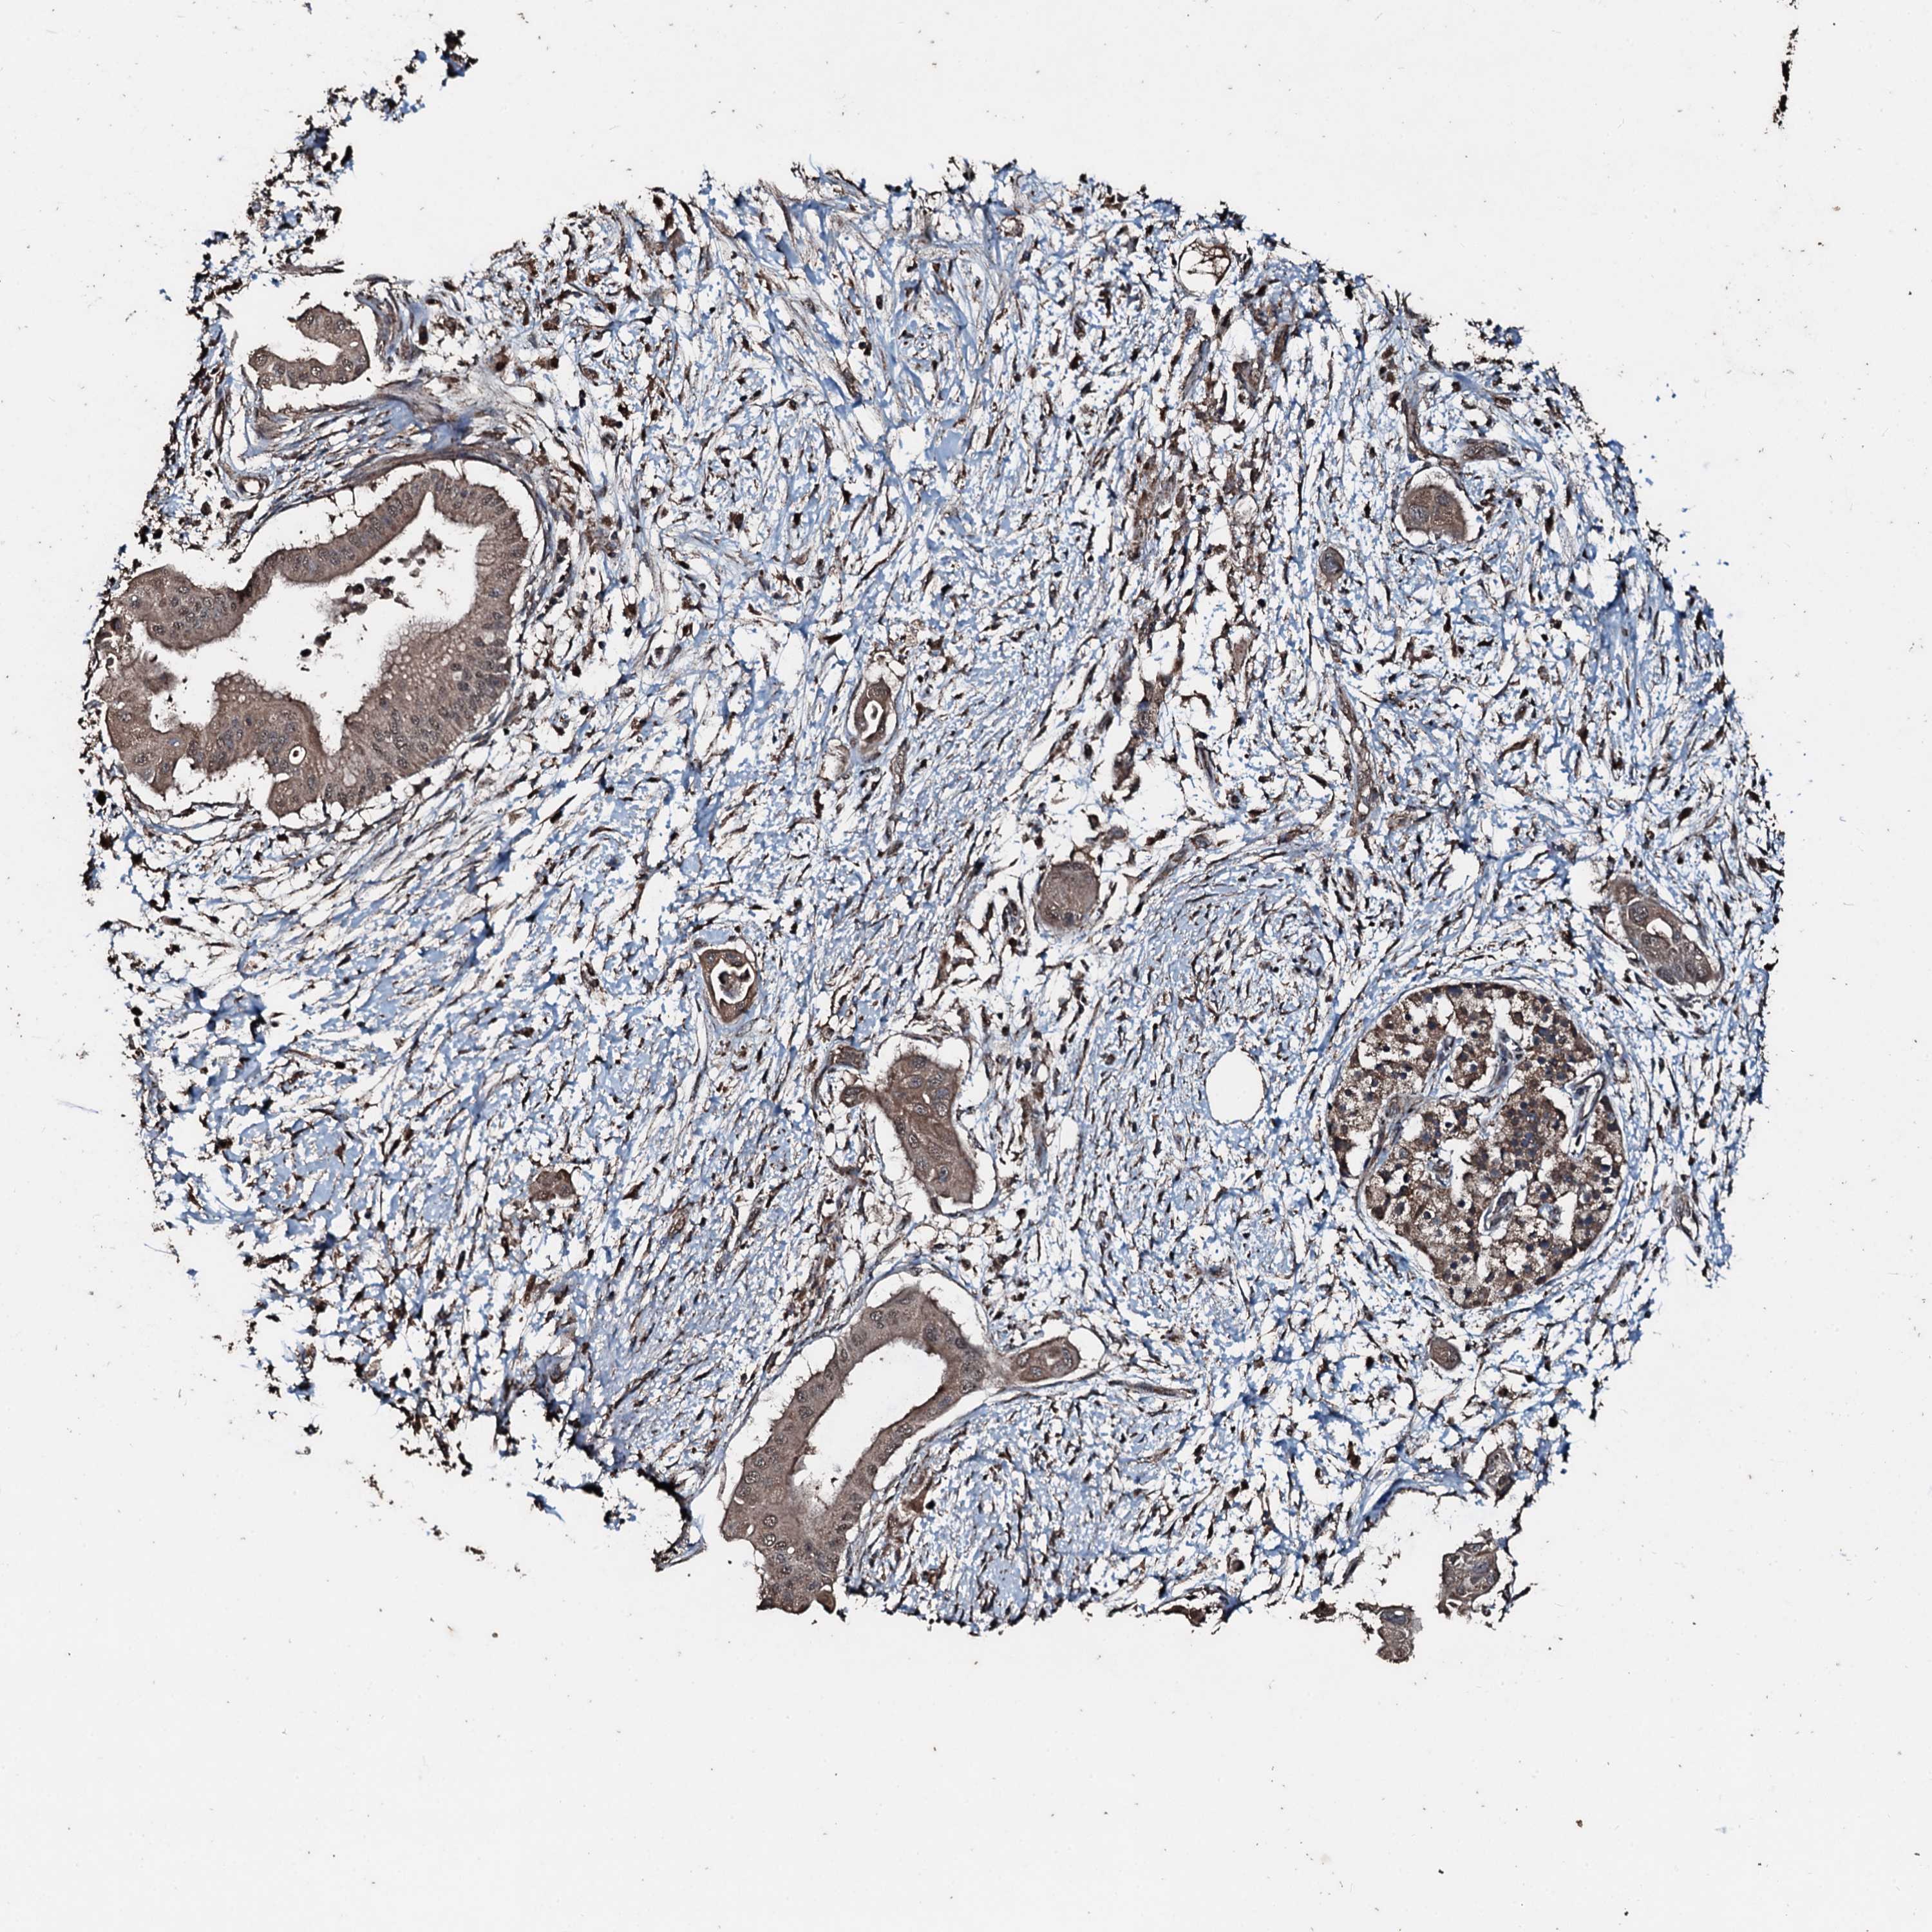

PANCREATIC CANCER - Protein expressioni

A mouse-over function shows sample information and annotation data. Click on an image to view it in a full screen mode. Samples can be filtered based on level of antibody staining by selecting one or several of the following categories: high, medium, low and not detected. The assay and annotation is described here.

Note that samples used for immunohistochemistry by the Human Protein Atlas do not correspond to samples in the TCGA dataset.

Antibody stainingi

Antibody staining in the annotated cell types in the current human tissue is reported as not detected, low, medium, or high, based on conventional immunohistochemistry profiling in selected tissues. This score is based on the combination of the staining intensity and fraction of stained cells.

Each image is clickable and will lead to virtual microscopy that enables deeper exploration of all samples and also displays staining intensity scores, fraction scores and subcellular localization as well as patient and tissue information for each sample.

Antibody HPA041168

Staining

High

Medium

Low

Not detected

Intensity

Strong

Moderate

Weak

Negative

Quantity

>75%

75%-25%

<25%

None

Location

Nuclear

Cytoplasmic/membranous

Cytoplasmic/membranous,nuclear

Adenocarcinoma, NOS